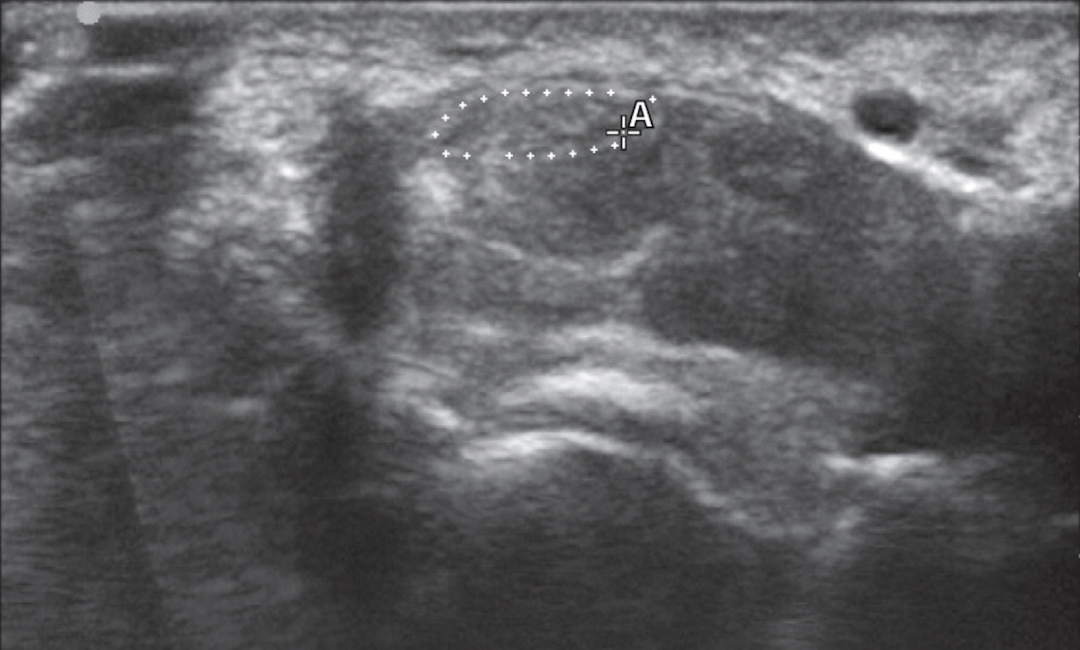

在進行EDX檢查后,立即用高分辨率超聲波對患者右手腕的正中神經(jīng)進行橫向成像,以測量腕管近端蝶形水平的截面積(圖1)。圖像顯示正中神經(jīng)增大,橫截面積為14平方毫米(而正常上限為11平方毫米)。

圖一

一名患有腕管綜合征的24歲男子的右手腕的橫向超聲圖像(病例1)。圖像在腕管近端豌豆骨水平,正中神經(jīng)(在 "A "左邊用白點勾勒)的橫截面積測量值為14 平方毫米。